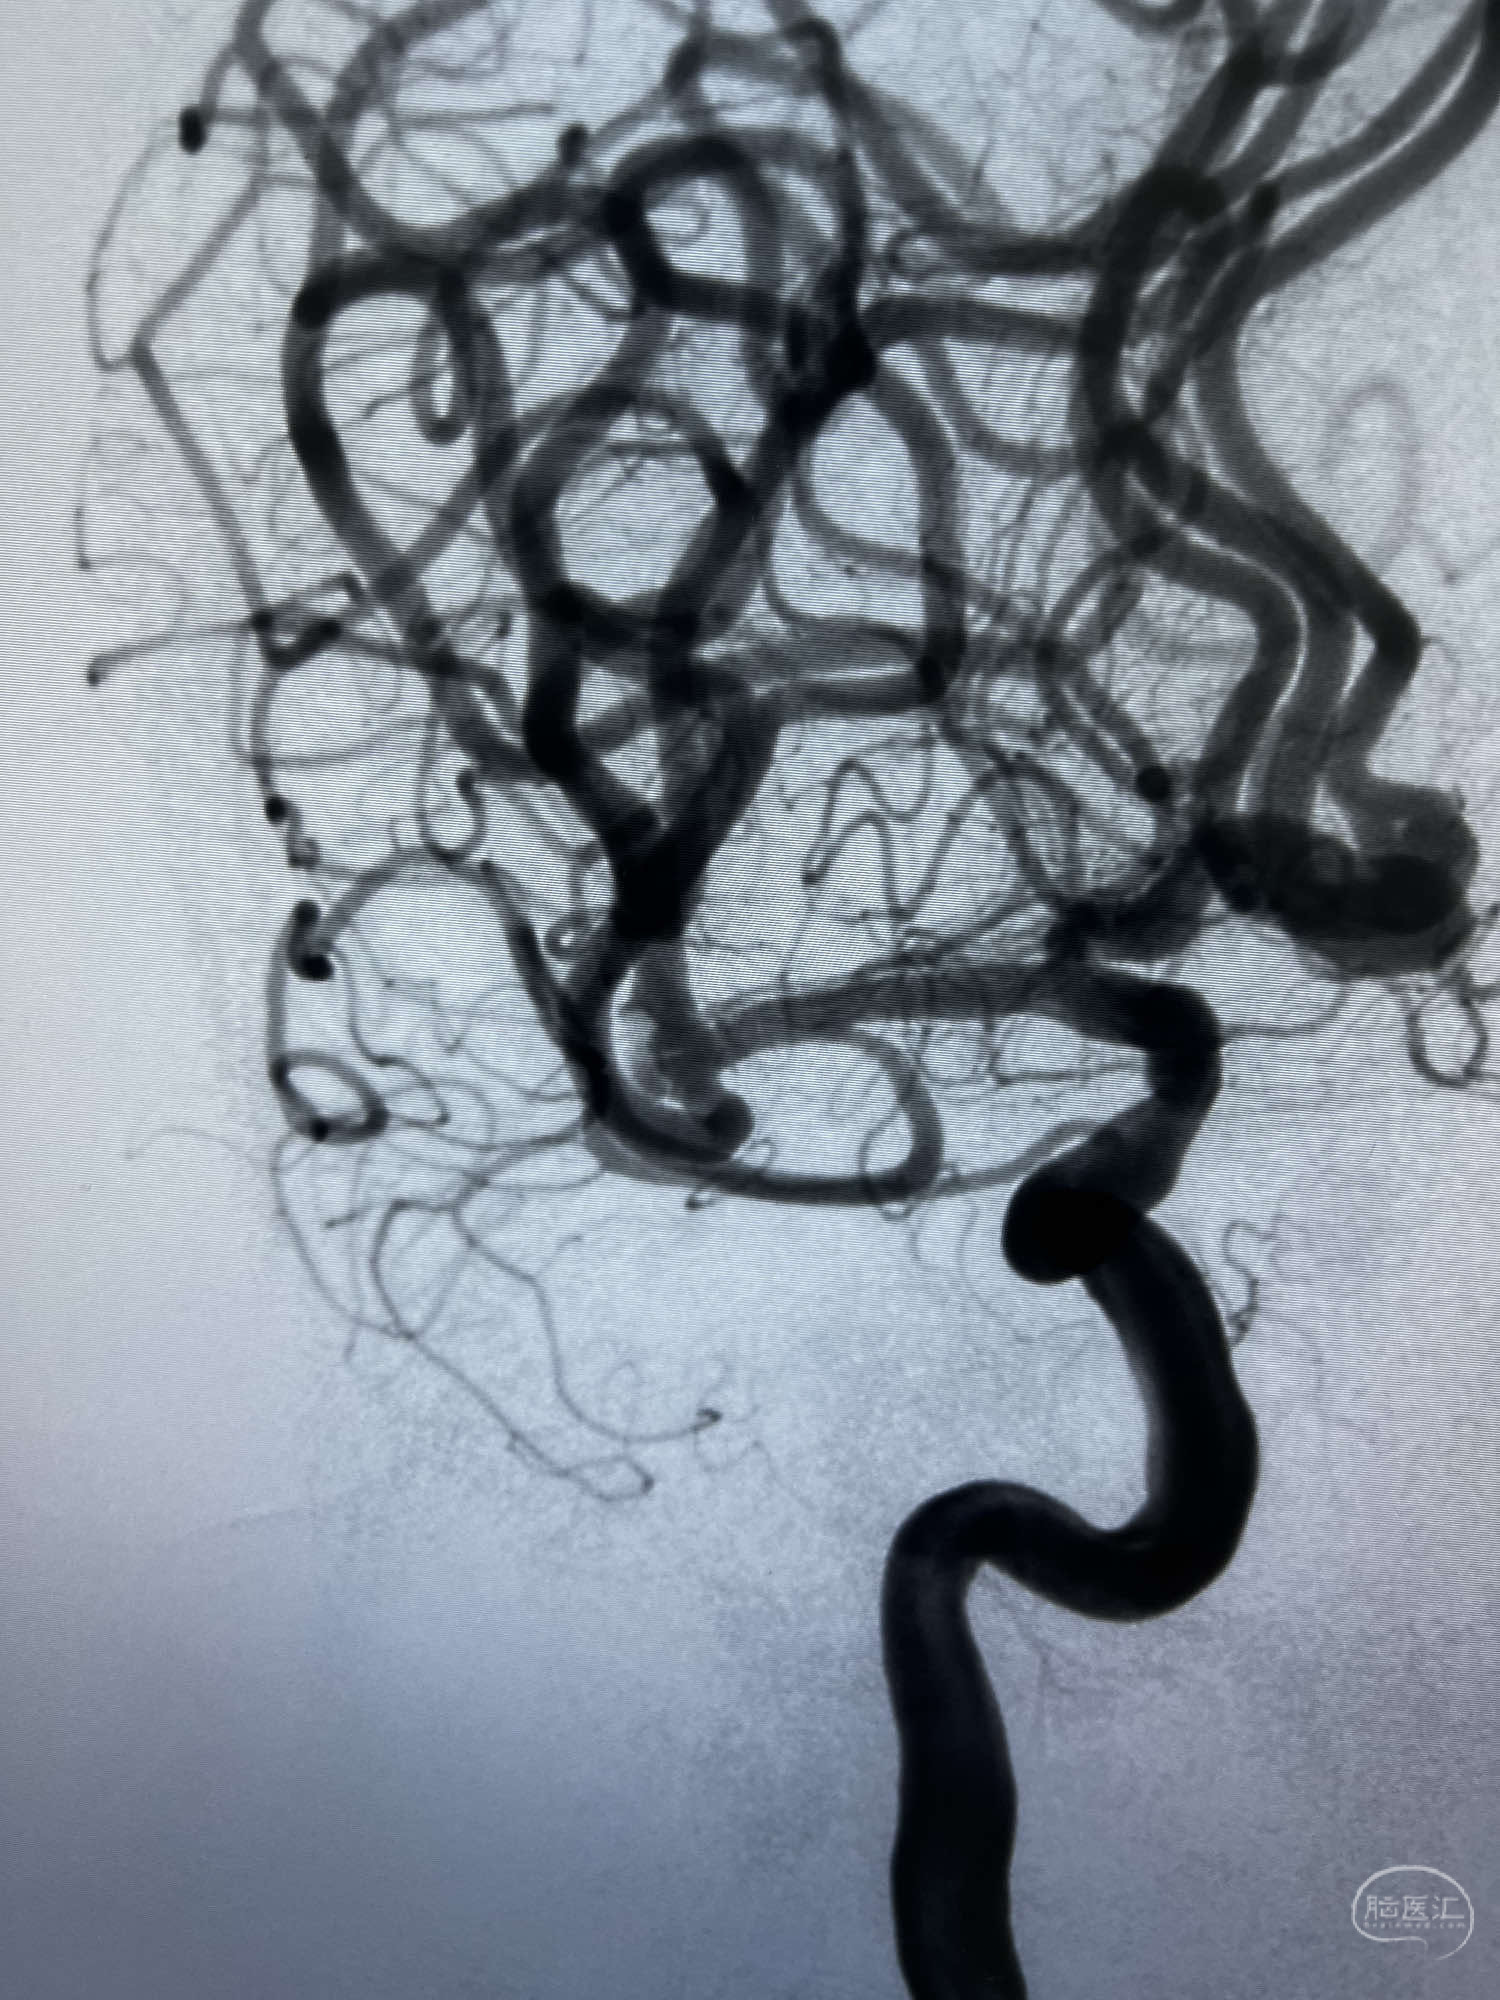

6F Neuromax➕6F115cm 心玮中间导管建立路径,sychro14微导丝➕VIA21超选至动脉瘤体内近中部,WEB5mmx3mm植入动脉瘤。

WEB瘤内扰流装置5mmx3mm经过“种子、萌芽、开花”三个阶段,打开后良好贴壁,动脉瘤内血液滞留,载瘤动脉通畅。WEB一步到位,通过瘤内扰流的方式起到栓塞动脉瘤的作用,避免了应用支架保护分支血管,简化了操作步骤,降低了术中血栓及出血的风险。